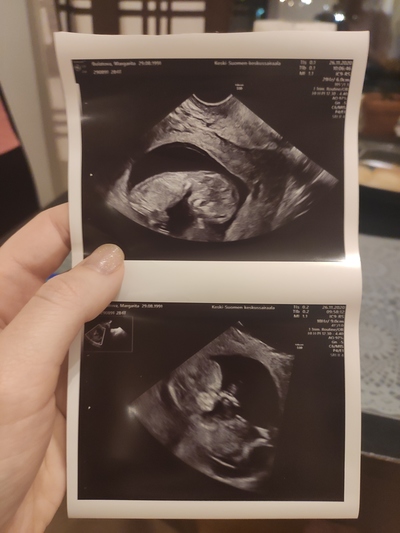

Вижу на мониторе маленького человечка с ручками, ножками и крошечными пальчиками( забегая вперед скажу, что эти пальчики теперь частенько наведываются в мои ночные кошмары).

Говорю врачу узи: «посмотрите-ка, уже настоящий человек!»

А она мне: «беременность замерла на 10 неделе, сердцебиения нет».